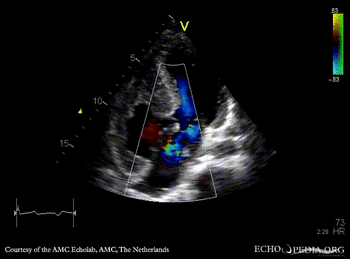

A4CH: color Doppler of AV valve regurgitation